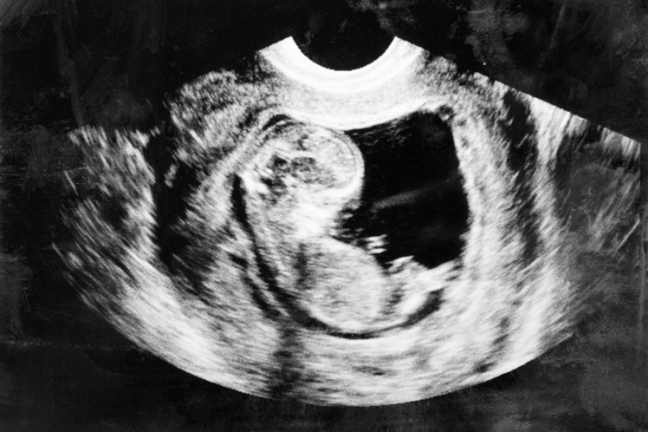

L’exemple le plus triste est celui d’un couple qui avait découvert la veille de Noël 2018 qu’ils attendaient un heureux évènement, mais à qui les médecins ont annoncé que leur petit garçon à naître présentait une « anomalie fœtale fatale ». Le 21 février 2019, le couple a passé une échographie à la clinique privée Merrion Fetal Health Clinic, où on leur a dit de passer un autre test pour des troubles potentiels tels que la trisomie 21 ou le syndrome d’Edward (également connu sous le nom de trisomie 18). Une semaine plus tard, les parents ont appris que leur garçon était atteint de trisomie 18. Cette condition est l’une des principales exceptions prévues par la législation sur l’avortement de 2018 du ministre de la Santé Simon Harris pour un avortement après le seuil de 12 semaines.

Abonnez-vous à notre chaîne Youtube !

Lors d’un test de suivi au Greater Glasgow Health Board, les parents ont appris une nouvelle fois que leur bébé était atteint de trisomie 18, et le choc s’est produit. Les médecins leur ont dit que leur garçon ne serait pas viable, qu’il présentait une « anomalie fœtale fatale », et on leur a conseillé d’avorter « en termes très clairs ». Il y avait un autre test qu’ils pouvaient faire — une analyse du caryotype — mais le couple affirme qu’on leur a dit de ne pas attendre les résultats et d’aller de l’avant avec un avortement. Le petit garçon a été tué au National Maternity Hospital le 14 mars 2019, à quinze semaines de gestation.